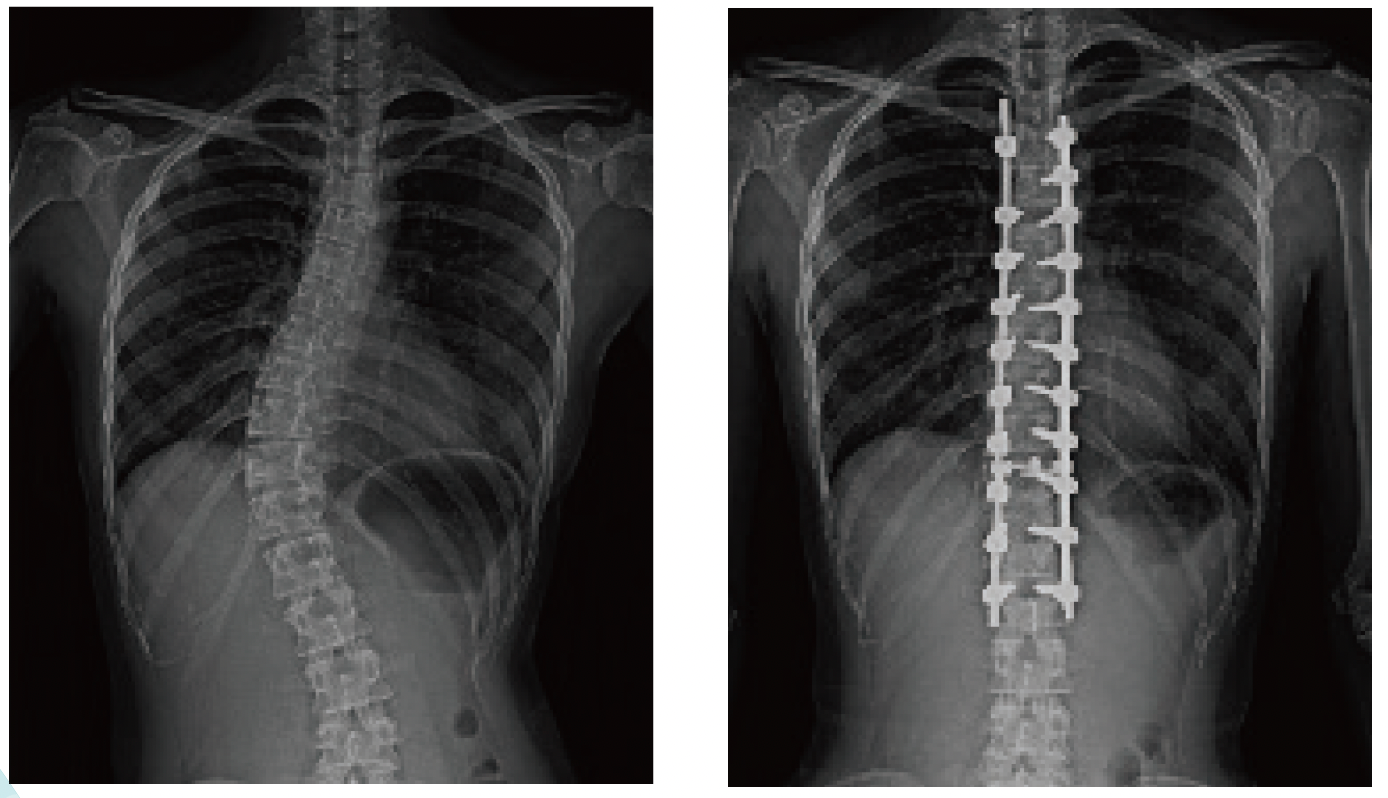

側弯矯正固定術

手術をより安全に行うために、当センターで は手術中に生理機能検査技師が常時、神経の 麻痺が生じていないかモニタリングを施行 しています。また、手術中に挿入する金属は ナビゲーションシステムを使用し安全に挿 入し、挿入後もO-arm(オーアーム)システム を使用してスクリューの位置を確認するこ とができます。側弯症のインプラント挿入 は、技術的に難易度が高くこれらの対策にて より安全に手術が行えるようにしています。